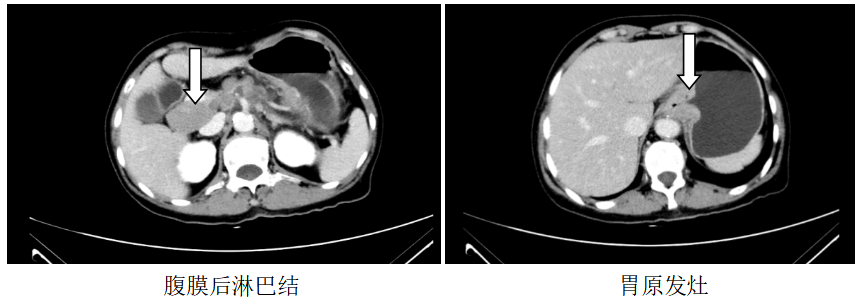

胸部CT:1、左锁骨区、左腋窝多发肿大淋巴结,考虑转移,建议随访,全腹CT:考虑食管胃交界癌累及胃周脂肪并腹腔腹膜后淋巴结多发转移(CT分期约T4aN3)。

图1.2019.7.5影像(基线评估)

诊断:食管胃交界腺癌腹腔、腹膜后、左腋窝、左锁骨区淋巴结转移脑转移(cT4aN3M1,IV期,HER2扩增,MSS,PD-L1-)